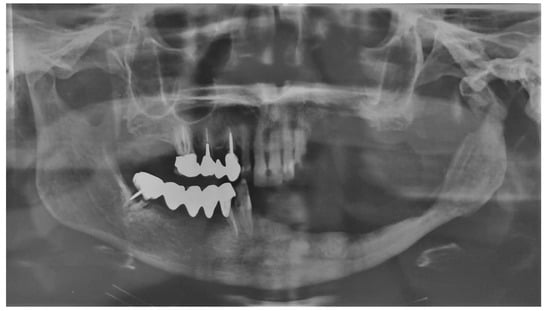

Group A showed higher complete healing cases when compared to group B (Figure 1, Figure 2, Figure 3 and Figure 4).

Figure 2. Group A patient. Radiological pre-operative assessment through cone beam computed tomography of a stage 2 maxillary and mandibular MRONJ. Maxillary view (A) and 3D reconstruction (B); mandibular view (C) and 3D reconstruction (D).

Figure 3. Post-operative follow-up at 6 months through orthopantomography.